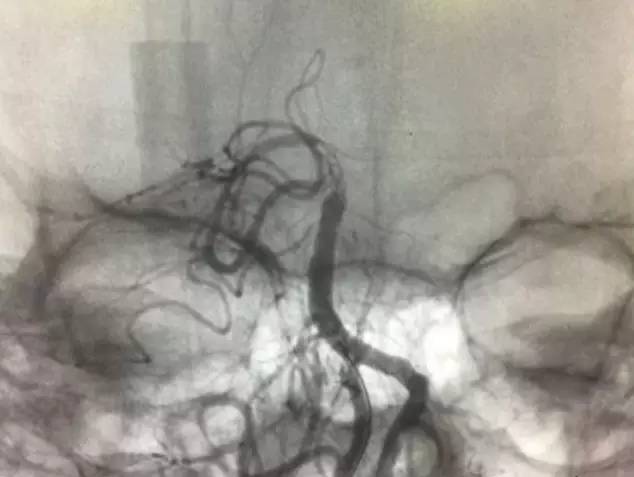

▼支架释放后,右大脑后及小脑上显影同时看到基底动脉的血栓,拉栓一次就再通。

此时手术是否结束?内心又开始纠结了,贪心的本性又暴露,如果左椎是急性闭塞那么打通之后给患者又多加一个保险,这样以后万一右椎有什么三长两短那么左椎还可以救命所以决定开通左椎:费了好大劲通过微导丝进入椎开口内,向上不能通过闭塞段考虑为陈旧性闭塞,遂即放弃开通!术后欣慰宁维持!